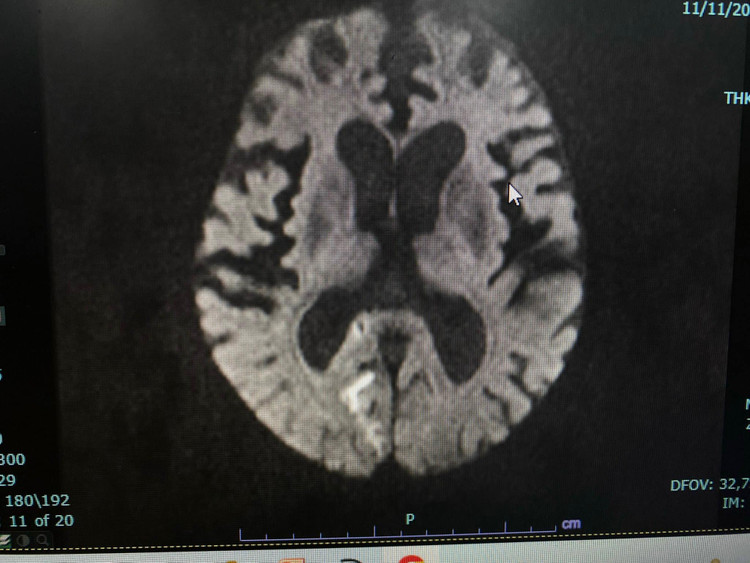

Bệnh nhân đã được khám và tư vấn chụp cộng hưởng từ sọ não: có hình ảnh tổn thương tiểu não, thân não do tắc thân nền nhưng quá giờ can thiệp. Bệnh nhân và gia đình đã bỏ qua thời gian vàng để cứu sống bệnh nhân.

| Hình ảnh tổn thương trên phim chụp |